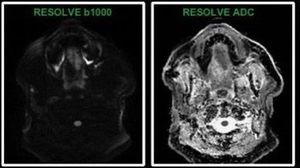

Head/neck is a difficult area for DW imaging due to local inhomogeneities (mouth movement, swallow, dental restoration materials, air, different types of tissues), which degrade image quality. Multi-shot Read-out Segmented Echo-Planar Imaging (RS-EPI) is a new, revolutionary technique for obtaining high-quality, distortion-minimized diffusion-weighted images of challenging body regions, including the head and neck area, in clinically acceptable acquisition times. Images courtesy of Nguyen Bac.